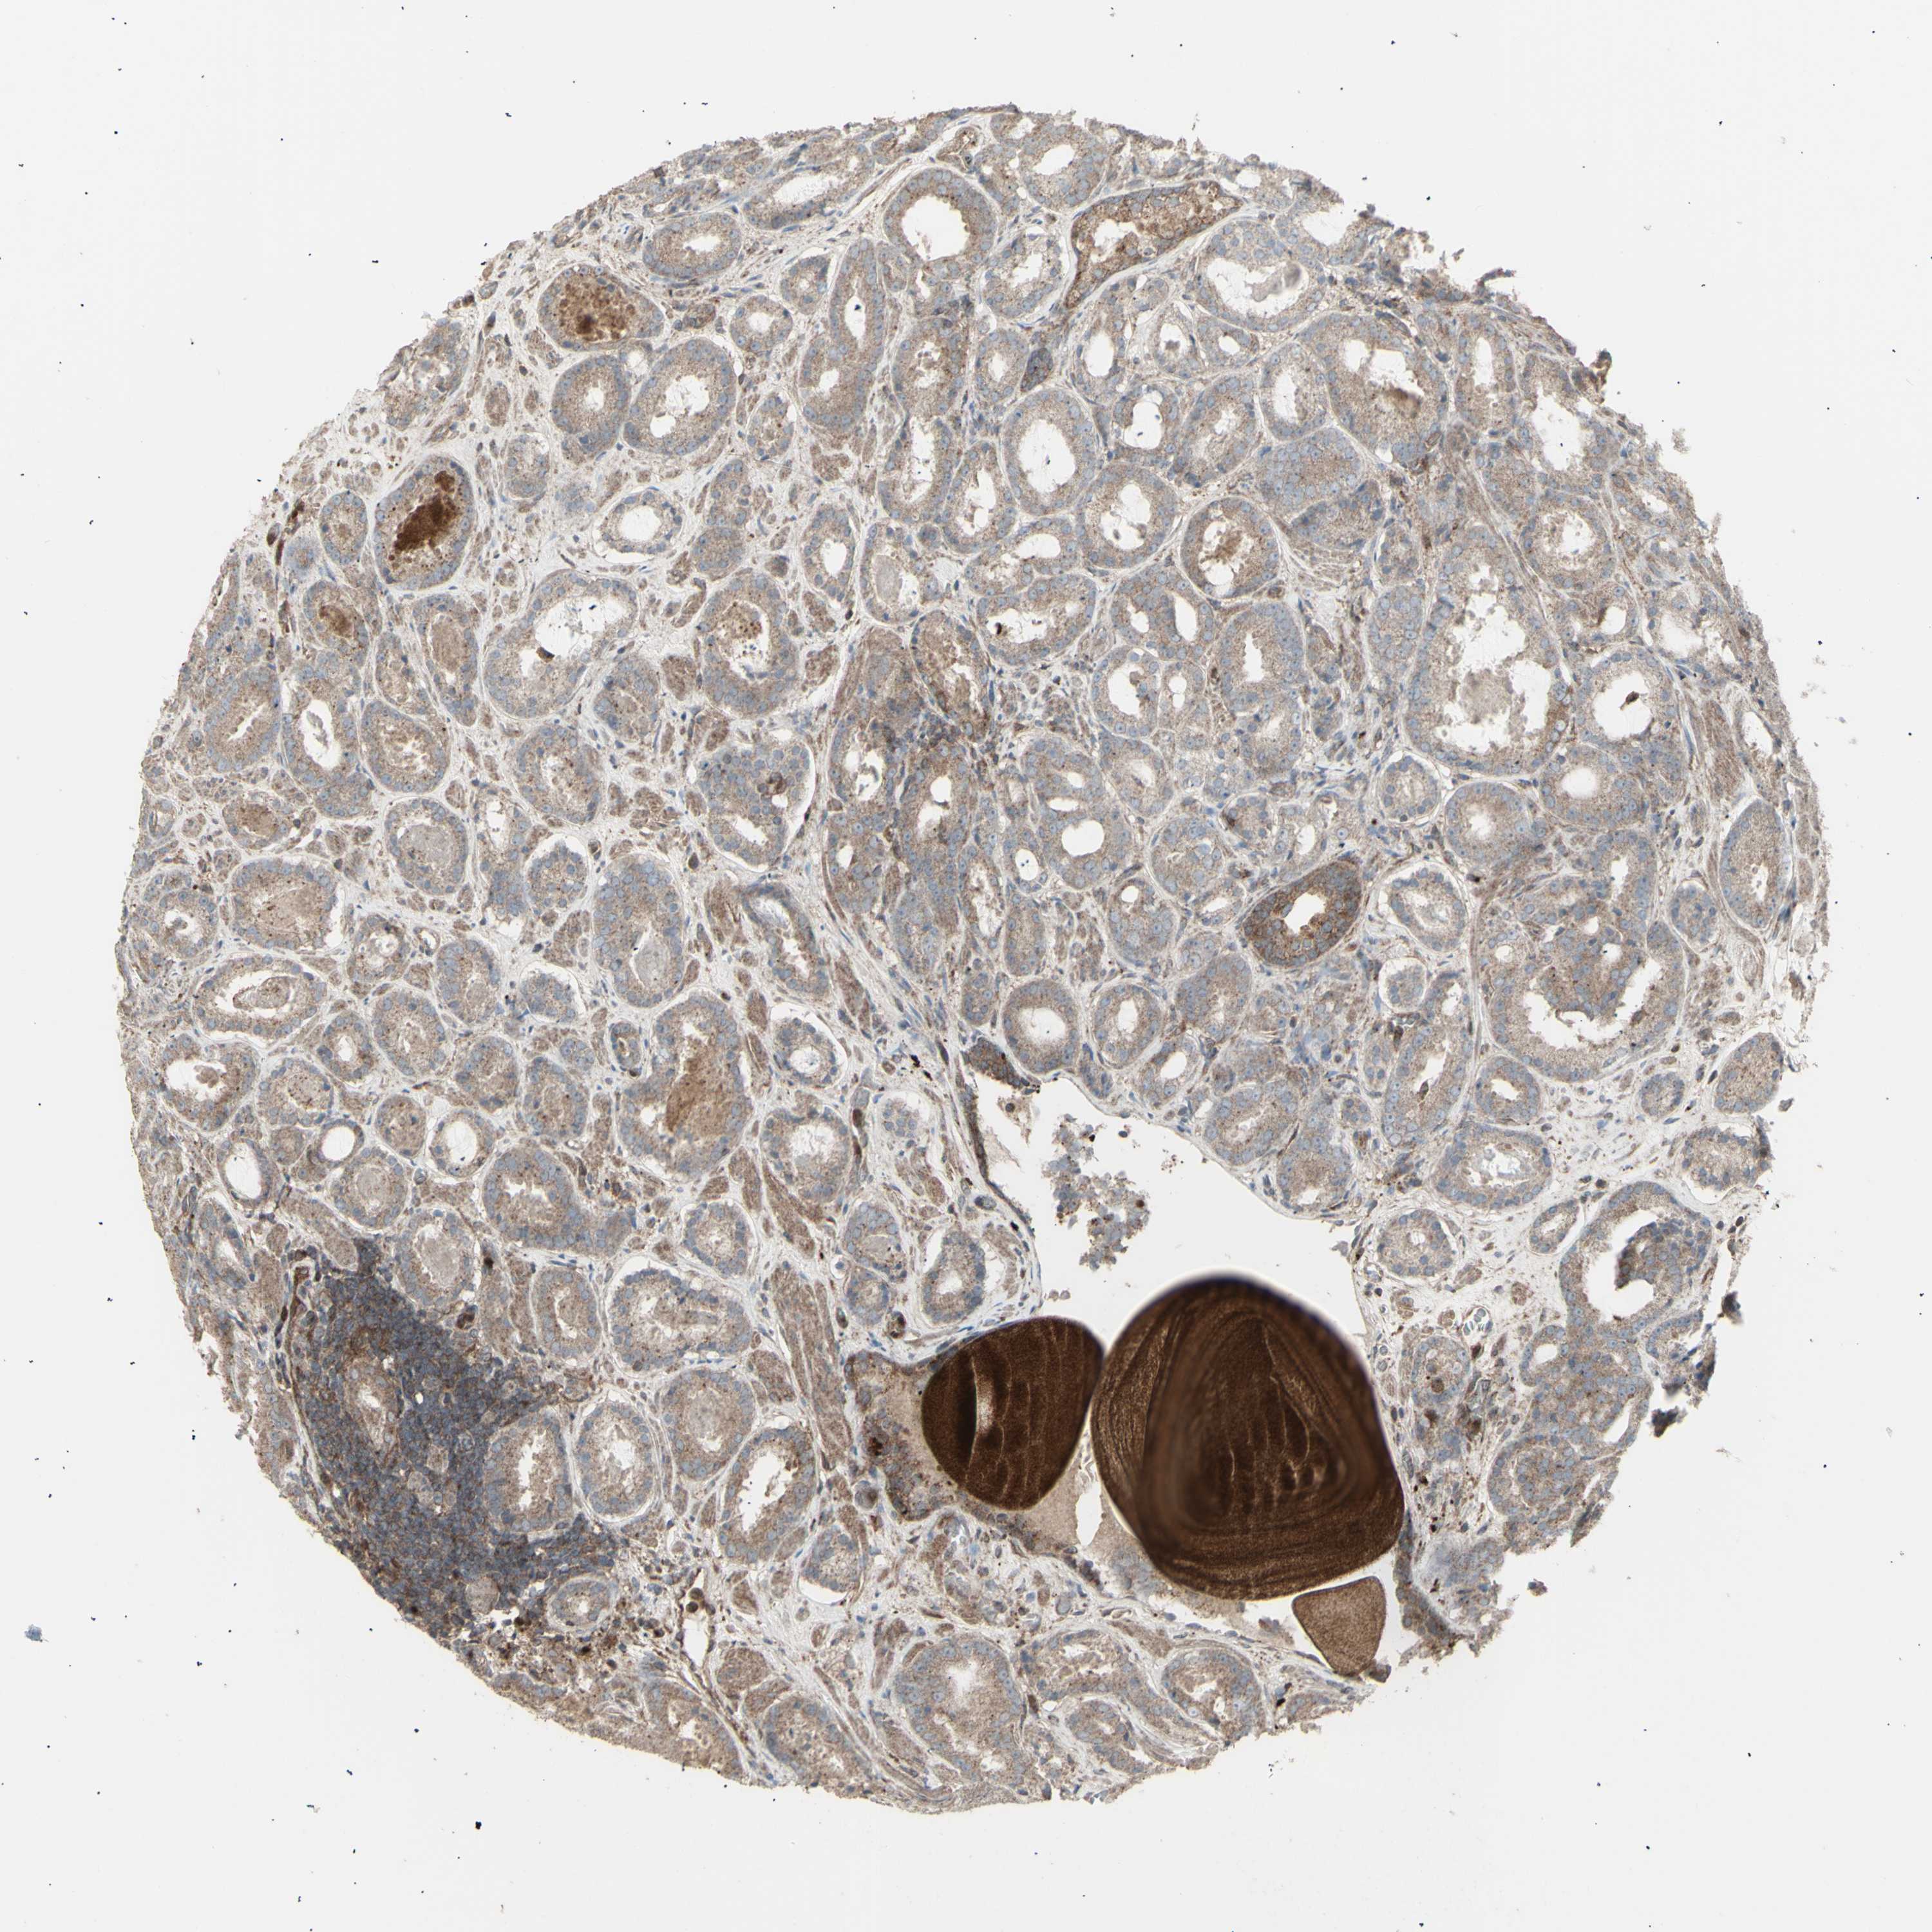

PROSTATE CANCER - Protein expressioni

A mouse-over function shows sample information and annotation data. Click on an image to view it in a full screen mode. Samples can be filtered based on level of antibody staining by selecting one or several of the following categories: high, medium, low and not detected. The assay and annotation is described here.

Antibody stainingi

Antibody staining in the annotated cell types in the current human tissue is reported as not detected, low, medium, or high, based on conventional immunohistochemistry profiling in selected tissues. This score is based on the combination of the staining intensity and fraction of stained cells.

Each image is clickable and will lead to virtual microscopy that enables deeper exploration of all samples and also displays staining intensity scores, fraction scores and subcellular localization as well as patient and tissue information for each sample.

Antibody HPA002633

Antibody HPA046758

Antibody CAB010906

Staining

High

Medium

Low

Not detected

Intensity

Strong

Moderate

Weak

Negative

Quantity

>75%

75%-25%

<25%

None

Location

Nuclear

Cytoplasmic/membranous

Cytoplasmic/membranous,nuclear

Adenocarcinoma, Medium grade

Adenocarcinoma, High grade

Adenocarcinoma, Low grade

Adenocarcinoma, NOS